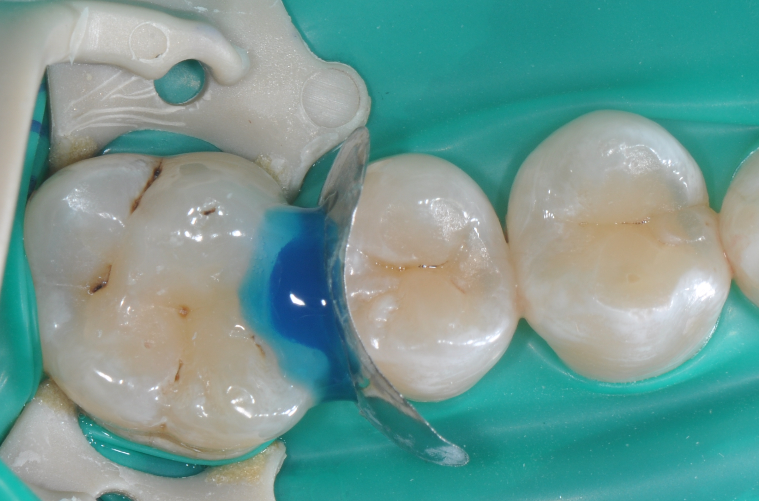

在以树脂充填为前提的案例中,无需过度制作颌面的鸠尾固位型,橡皮障下隔湿,是临床粘结操作技术成功的重要保障。酸蚀剂在使用的时候,需要尽量避免对邻牙的伤害

◆该成形片能更好的将龈缘区域的边缘封闭性做的更好。尤其是在邻面区域,涂布第六代粘结剂,固化粘结剂之后,配合高填料流体树脂和后牙专用树脂进行该洞形的充填。